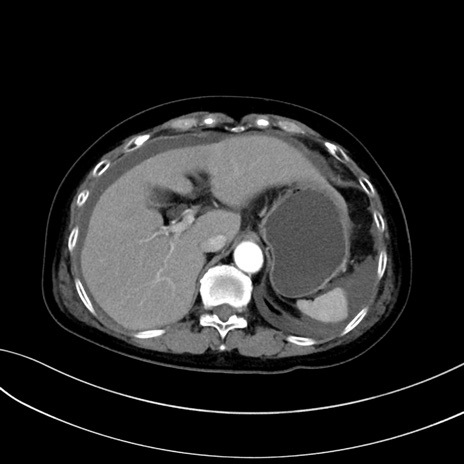

症例13 CT(横断像)1日半後